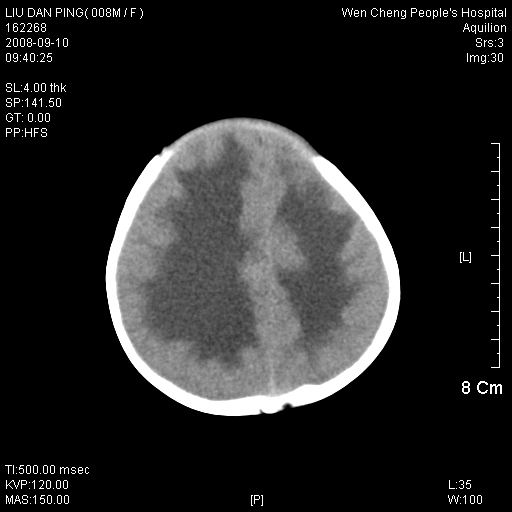

以下是引用卜一在2008-9-10 16:21:00的发言:[br]髓母细胞瘤伴梗阻性脑积水!支持![br]髓母细胞瘤特点:—般直径大于3.5cm,位于后颅凹中线之小脑蚓部。累及上蚓部的肿瘤延伸到小脑幕切迹之上,ct平扫肿瘤多呈均匀一致的高或等密度病灶,增强检查呈均匀一致的强化。病灶中有小坏死时,平扫亦可呈不均匀之混杂密度,注药后有增强。[br]

以下是引用zjzjr在2008-9-10 15:09:00的发言:[br]髓母细胞瘤伴梗阻性脑积水.